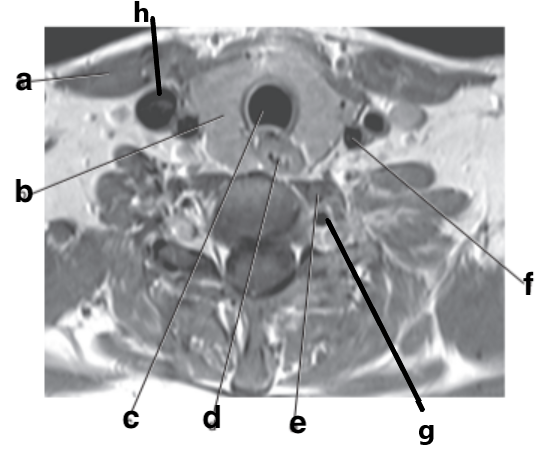

What is letter e?

Subclavian artery

What is letter f?

Vertebral artery

What is letter b?

Left ventricle

What is letter a?

What is letter c?

Aortic arch

Which letter is the left common carotid?

a

Esophagus

Trachea

Which letter is the Right vertebral artery?

f